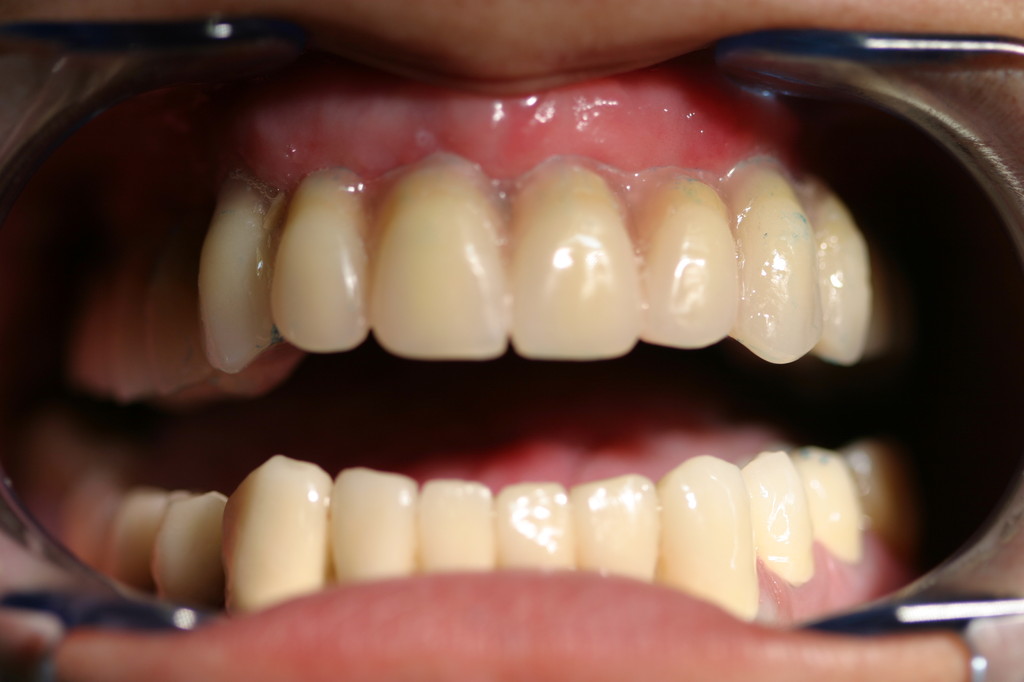

REHABILITACIÓN ESTÉTICA CON IMPLANTES.